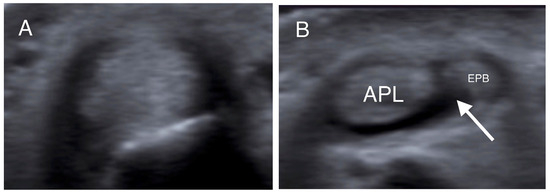

- Choi, S.J.; Ahn, J.H.; Lee, Y.J.; Ryu, D.S.; Lee, J.H.; Jung, S.M.; Park, M.S.; Lee, K.W. De Quervain Disease: US Identification of Anatomic Variations in the First Extensor Compartment with an Emphasis on Subcompartmentalization. Radiology 2011, 260, 480–486. [Google Scholar] [CrossRef]

- Kwon, B.C.; Choi, S.J.; Koh, S.H.; Shin, D.J.; Baek, G.H. Sonographic Identification of the Intracompartmental Septum in de Quervain’s Disease. Clin. Orthop. Relat. Res. 2010, 468, 2129–2134. [Google Scholar] [CrossRef]

| Intracompartmental septum | 27 (54%) |

| Double groove | 12 (24%) |